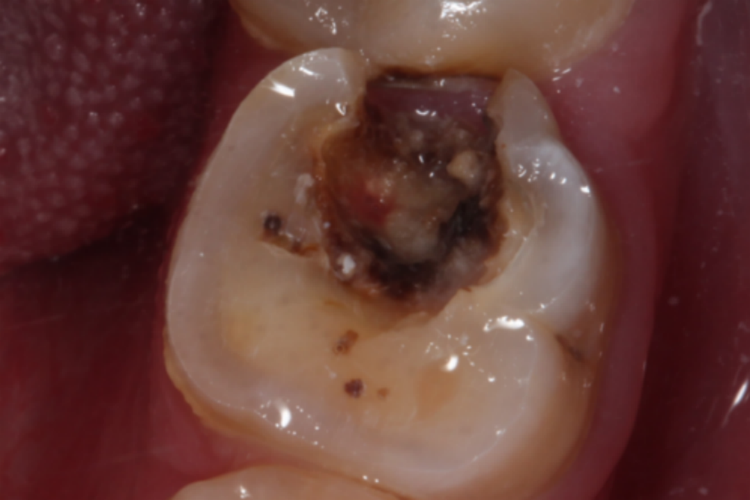

在临床主要通过局部症状表现来判断牙髓是否外露,外露可在牙洞内见糜烂、出血、红肿,并且探痛明显,多由龋病导致。

在临床判断牙髓是否外露,主要是通过局部症状表现,由于牙髓位于牙腔内,由结缔组织、神经和血管共同组成,而且感觉神经末梢丰富,一旦出现异常就会引起剧烈疼痛。因此如果在牙洞内见糜烂、出血、红肿,并且触痛明显,说明有牙髓外露的情况,需及时到医院就诊。